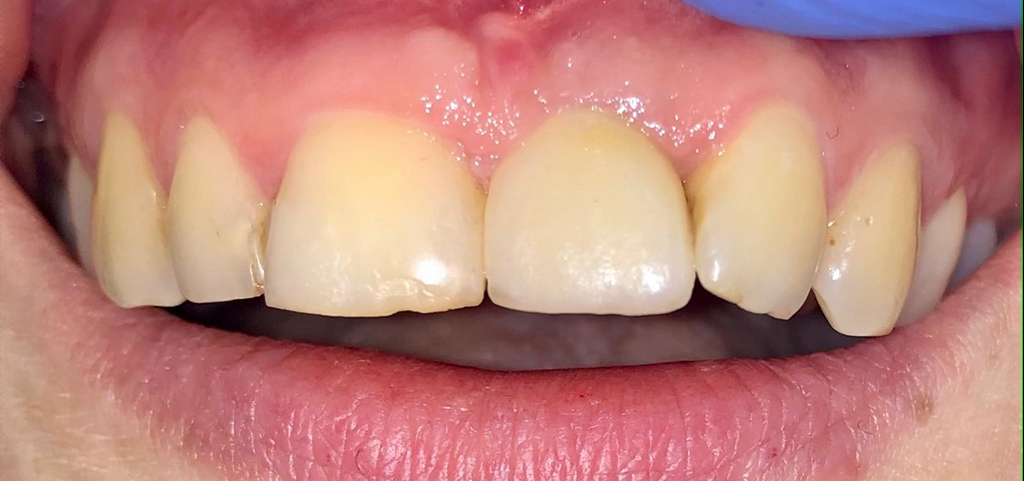

Wygląd w jamie ustnej po zabiegu rekonstrukcji kostnej okolicy górnej lewej jedynki i osadzeniu korony na implancie

wyglad jamy ustnej po zabiegu rekonstrukcji

Chirurgia: dr n.med. Ewa Zawiślak

Protetyka: lek. stom. Katarzyna Wojtuściszyn-Ordyniec